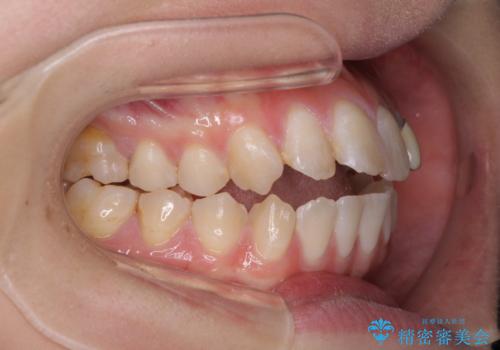

開咬を治す インビザラインによる矯正治療

- 上下前歯の開咬を気にして来院された患者様です。

開咬はインビザラインを用いると有意に改善ができるため、インビザラインによる矯正治療を行うこととしました。

途中1年8ヶ月ほど来院されず、久しぶりの来院後は治療が面倒とのことで、前歯の叢生や隙間に不十分な点が残った状態での終了となりました。